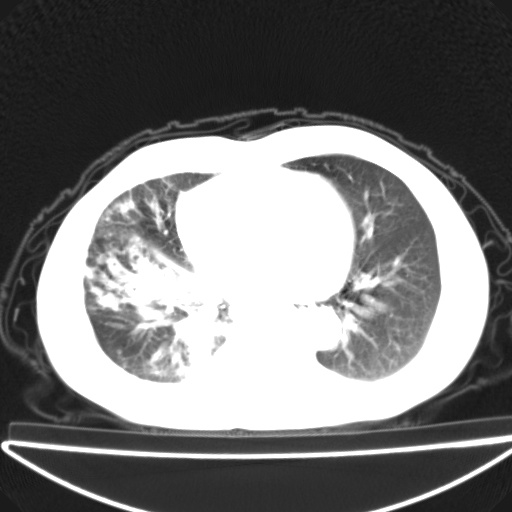

以下是引用jsgdoctor在2008-11-6 22:12:00的发言:[br]右主支气管壁明显增厚,管腔狭窄.考虑为右侧中央型肺癌伴阻塞性炎症\\肺脓肿.

以下是引用zjzjr在2008-11-6 20:25:00的发言:[br]中心型肺ca,合并阻塞性肺炎

以下是引用zsl6918在2008-11-6 19:43:00的发言:[br]右侧中心性肺癌(鳞癌)